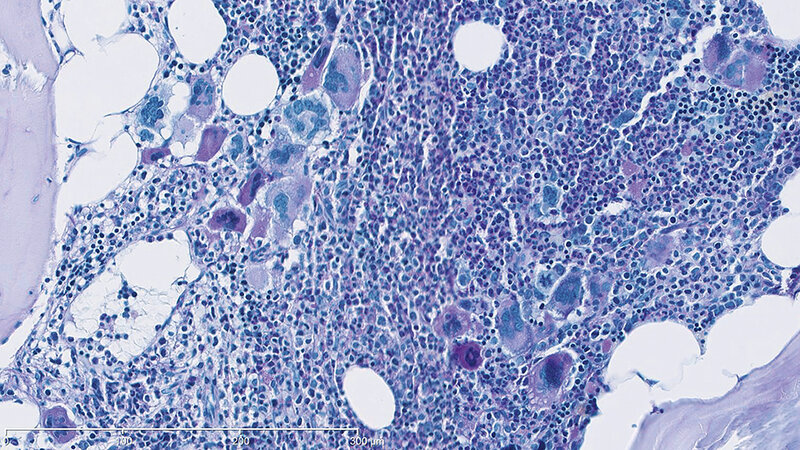

Bereits ein vermehrter körperlicher Stress kann mit einer erhöhten Plättchenzahl einhergehen, bedingt durch die Ausschüttung von Thrombopoetin (TPO) mit Steigerung der Thrombopoese im Knochenmark. Daneben können maligne hämatologische Erkrankungen für eine ausgeprägte Thrombozytenvermehrung verantwortlich sein (primäre Thrombozytose). Hierbei erfolgt die Thrombozytenvermehrung unkontrolliert, TPO-unabhängig. Eine wesentliche Aufgabe besteht in der Unterscheidung reaktiver versus maligner Genese. Hierfür kann die Zytologie hilfreich sein. In diesem Beitrag sollen einige Merkmale reaktiver und maligner Thrombozytosen dargestellt werden.